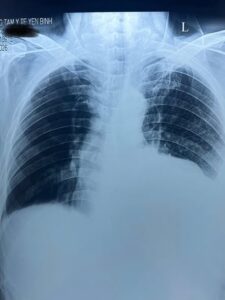

Kết quả thăm dò cho thấy bệnh nhân bị tràn dịch màng phổi hai bên. Trước tình trạng khó thở nặng, các bác sĩ đã kịp thời thực hiện thủ thuật chọc dịch màng phổi cấp cứu, giúp giải phóng dịch, cải thiện thông khí phổi và giảm nhanh các triệu chứng cho người bệnh.